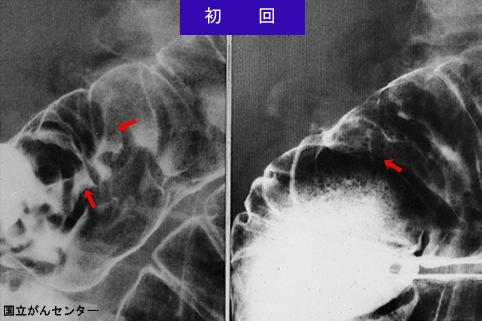

질환(병리주체)의 분류 악성 상피성종양/선암

부위(장기별) 십이지장/하행각

검사방법 X-P

종양의 육안분류 0형(표재형)/I형(Is)

종양의 최대경(밀리미터) 25~29

종양의 심달도 m